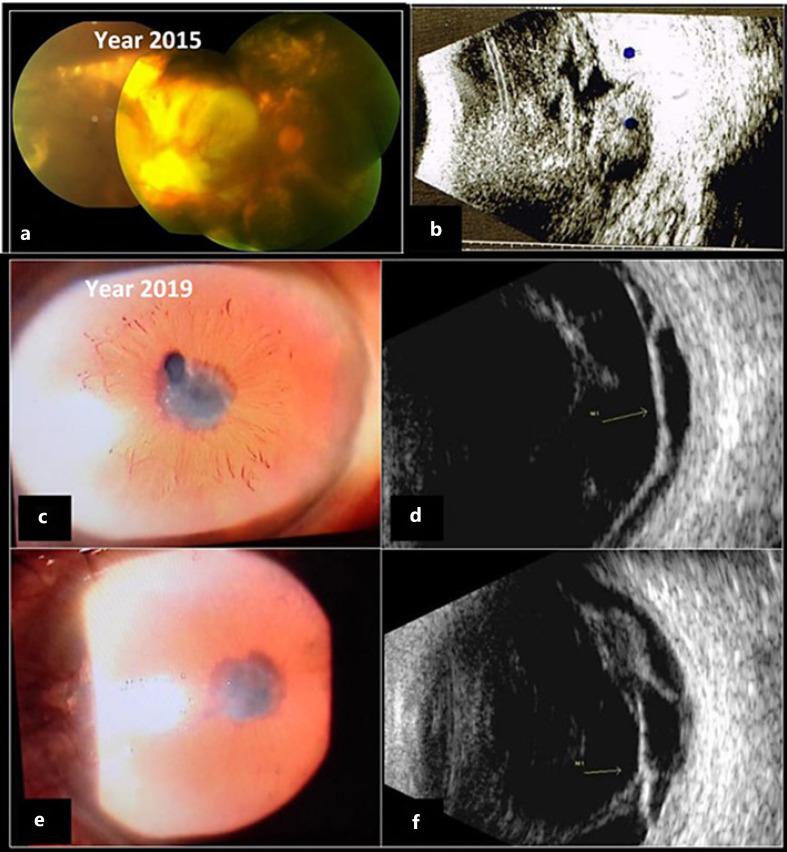

We report 2 cases of an aggressive choroidal neovascularization phenotype. A 77-year-old hypertensive woman, with a 4-year history of visual loss in her left eye, due to vitreous hemorrhage associated with a dome-shaped mass lesion underwent pars plana vitrectomy. An extensive subretinal hemorrhage was found, associated with extensive subretinal fibrosis, which was treated with endophotocoagulation and intravitreal injection of anti-VEGF. Best-corrected visual acuity after surgery was light perception. A 74-year-old woman with a 4-year history of treatment for choroidal neovascularization in both eyes presented with an extensive subretinal hemorrhage associated with exudation in the temporal peripheral retina. Lesions became larger despite monthly intravitreal anti-VEGF injections (14 injections) and verteporfin photodynamic therapy in both eyes. Throughout the years, the choroidal neovascular lesion continued to enlarge until it developed a severe vitreous hemorrhage. The patient rejected treatment and ended up with no light perception at the end of the follow-up (8 years). A rare severe choroidal neovascularization phenotype is presented here and would be considered to be at the aggressive extreme of the spectrum of a neovascular age-related macular degeneration or polypoidal choroidal vasculopathy that presents massive hemorrhage and exudation as much as in the posterior pole as in the peripheral retina.

我们报告2例侵袭性脉络膜新生血管表型病例。一名77岁的高血压女性,左眼有4年视力丧失史,因与穹窿状肿块病变相关的玻璃体积血接受了玻璃体切割术。发现广泛的视网膜下出血,伴有广泛的视网膜下纤维化,采用眼内光凝和玻璃体内注射抗VEGF进行治疗。术后最佳矫正视力为光感。一名74岁女性,双眼有4年脉络膜新生血管治疗史,出现广泛的视网膜下出血,伴有颞侧周边视网膜渗出。尽管每月进行玻璃体内抗VEGF注射(共14次)以及双眼进行维替泊芬光动力治疗,病变仍不断增大。多年来,脉络膜新生血管病变持续扩大,直至发生严重的玻璃体积血。患者拒绝治疗,随访(8年)结束时最终无光感。本文展示了一种罕见的严重脉络膜新生血管表型,可被认为处于新生血管性年龄相关性黄斑变性或息肉状脉络膜血管病变谱系的侵袭性极端,表现为后极部和周边视网膜均出现大量出血和渗出。